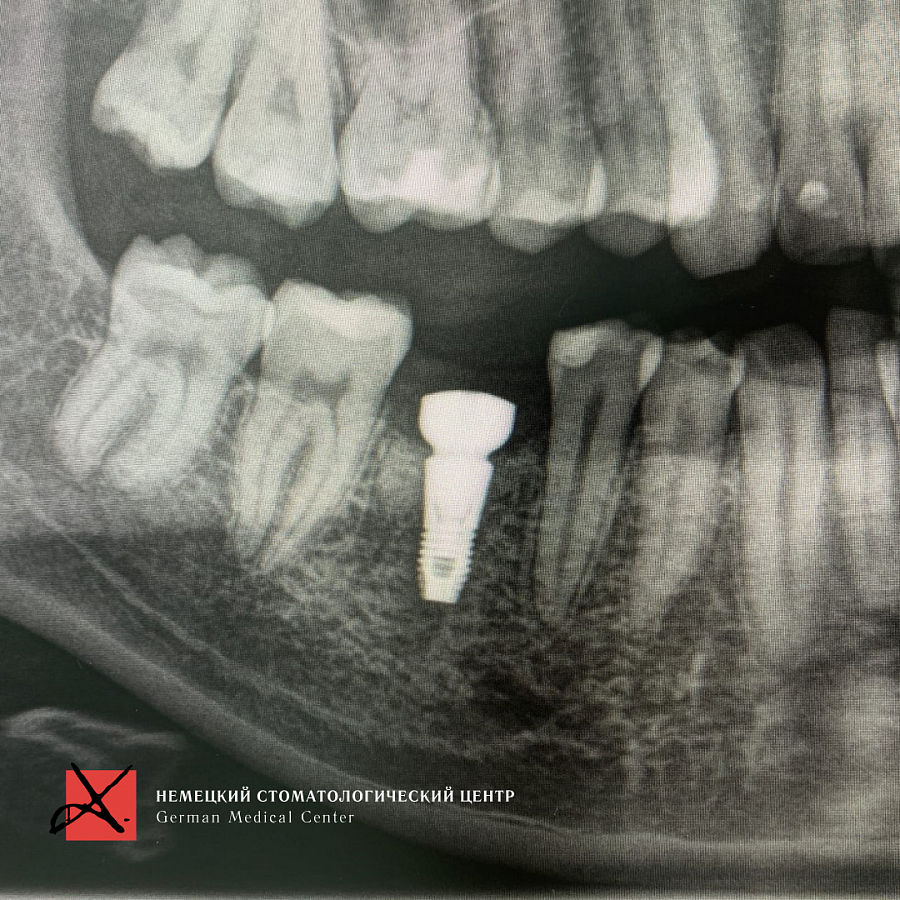

Пациент направлен врачом-терапевтом для удаления зуба 46 (нижний шестой зуб справа) и одновременной постановки имплантата.

Зуб был фрагментирован, чтобы удаление прошло максимально атравматично, то есть без повреждения окружающих костных стенок. После удаления установлен имплантат. Операция прошла успешно, пациенту уже установлена зубная коронка.